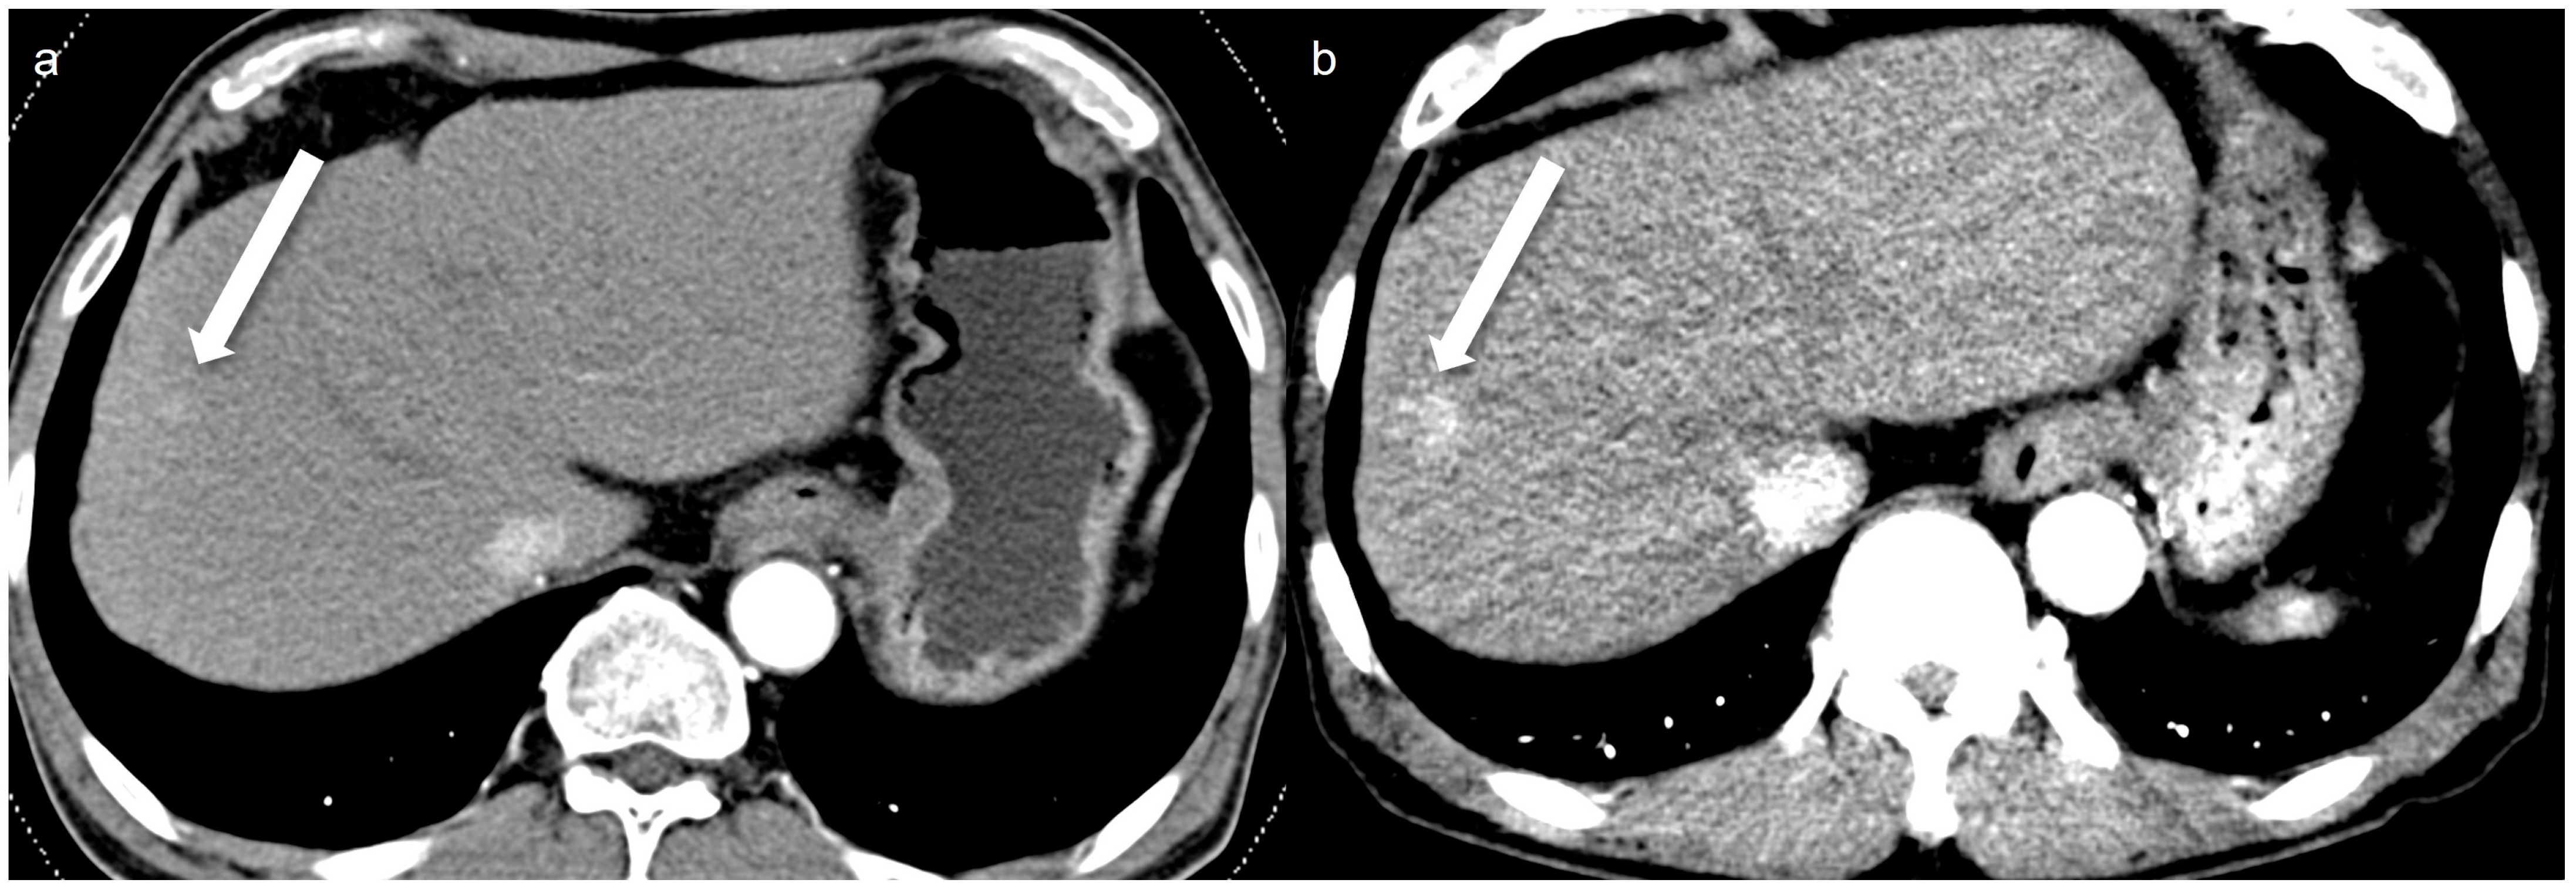

- Lee, H.J.; Kim, J.S.; Lee, J.K.; Lee, H.A.; Pak, S. Ultra-low-dose hepatic multiphase CT using deep learning-based image reconstruction algorithm focused on arterial phase in chronic liver disease: A non-inferiority study. Eur. J. Radiol. 2023, 159, 110659. [Google Scholar] [CrossRef]

- Lim, Y.; Kim, J.S.; Lee, H.J.; Lee, J.K.; Lee, H.A.; Park, C. Image Quality and Lesion Detectability of Low-Concentration Iodine Contrast and Low Radiation Hepatic Multiphase CT Using a Deep-Learning-Based Contrast-Boosting Model in Chronic Liver Disease Patients. Diagnostics 2024, 14, 2308. [Google Scholar] [CrossRef]